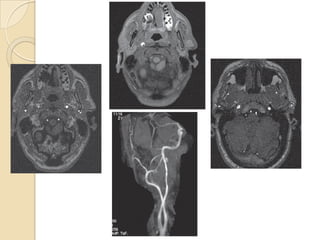

Carotid orVertebral artery dissection

 Catheter angiography has been traditionally used for

diagnosis of carotid dissection.

 MRI +fat saturation along with 3D TOF MRA characterise

dissecting hematoma, associated pseudo-aneurysm & length

and caliber of residual patent lumen.

 MRI with MRA is currently the investigation of choice for

suspected dissection.

 Not nearly as helpful in vertebral artery dissections

CAROTID ARTERY DISSECTION